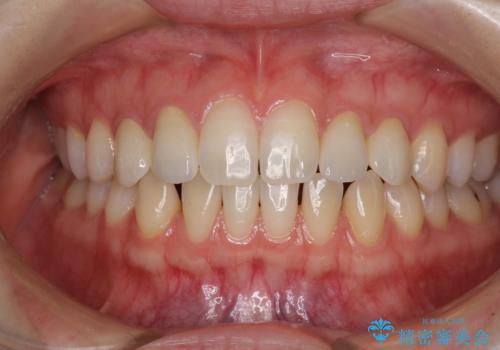

- 前歯の奇形や欠損、乳歯残存などによる審美障害を気にして来院された患者様です。

正中の隙間は矯正治療により閉じ、左右の4歯はオールセラミッククラウンにて補綴することとしました。

前歯2本もセラミッククラウンを装着することで隙間を閉じる治療方法もあるかと思いますが、健全な歯を削る必要は全くなく、矯正治療で対応することが望ましい治療であると考えます。